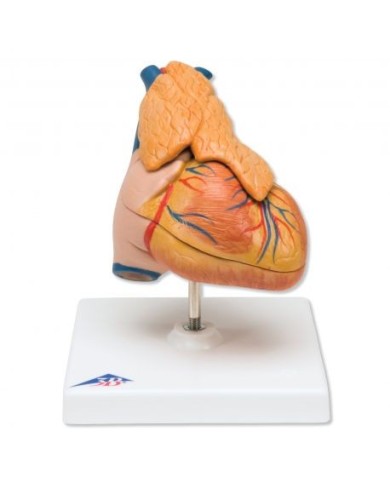

I modellini anatomici di cuore umano sono strumenti indispensabili per uno studio corretto dell'anatomia del cuore umano.

Su Tuttoanatomia trovi la più ampia selezione di prodotti esistente sul web, che va dai cuori normali ai cuori affetti da patologie, per aiutarti a comprendere come le patologie cardiache influiscono e modificano la struttura anatomica cardiaca.

Inoltre nella categoria sono presenti anche i modellini anatomici di cuore con bypass e con sistema di conduzione, fino ai modelli anatomici comparativi di patologie del cuore.